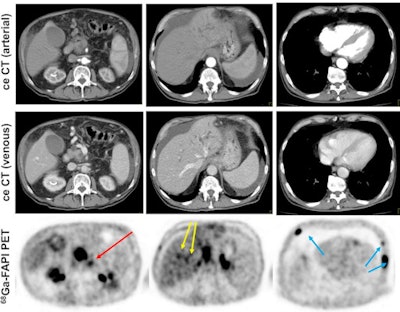

PDAC consists of cancer cells that express fibroblast activation protein (FAP). By adding a FAP inhibitor (FAPI) labeled with gallium-68 to PET/CT imaging, more than half of the PDAC patients in this study had their cancer more accurately staged or restaged, compared with results from contrast-enhanced CT.

The researchers found that Ga-68-FAPI-PET/CT provided new TNM findings for 10 of 19 PDAC patients (53%), which included the upstaging of eight of 12 patients (67%) with recurrent or progressive disease, while one patient's (8%) recurrent or progressive cancer was downgraded. Among seven PADC patients with primary disease, one case out of seven (14%) was upstaged; no patients were downstaged.

"In all cases, changes in staging were caused by the detection of new or additional distant metastases in one or more organ systems," the authors added. They also found a "markedly elevated uptake" of Ga-68-FAPI in most PDAC patients as soon as one hour after administration.

"Analyses of tracer biodistribution demonstrated a high FAPI uptake in primary PDAC as well as lymph nodes and distant metastases, whereas healthy tissues have negligible background activity," they wrote. "This leads to excellent tumor/background ratios for PDAC, similar to those shown by previous studies on FAPI-PET/CT in PDAC and other tumors."